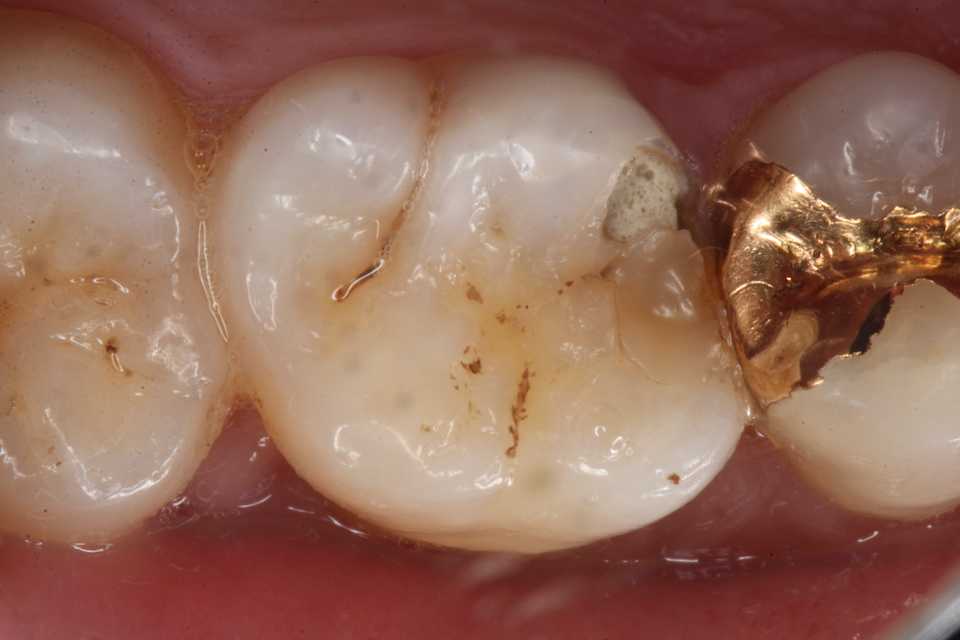

30代男性、左上7、近心CR2次カリエス(当院での処置ではない)、外傷性咬合前回とは違う方で、前回の方は政治家でしたが、今回の方は陶芸家です。いずれも歯を食いしばって頑張っておられるのでしょう。CRは剥がれやすく、また虫歯になってしまうと言われますが、そうでもない。ちゃんとやれば長持ちする。ただ術者の熟練度が高く、適正な材料を使ったとしても、患者に外傷性咬合があると2次カリエスが起こる。前回もそうだが、外傷性咬合があるとCRに限らずトラブルは起こりやすい。急速進行型の虫歯になり、内部に深く虫歯が進行する。では時系列でどうぞCRが脱離すると内部が虫歯になっていて、食べ物がはさまるので気が付く。食渣を除去するとすでに歯肉が虫歯の穴に迷入し始めている。歯肉を電気メスで除去したが、出血のコントロールが難しかったので、CR充填は次回にすることにした。水硬性セメントとデュラシールでカバー1週間後に治療再開。この方はご近所なのですぐに来てもらえる。前回の方は東京在住なので、簡単には来られないので、出血してもその場でなんとかするしかない。軟化象牙質を全部除去すると露髄しそうなので、α-TCPの再硬化作用に期待することにした。1次CR。1番奥の7番なのでCRでの処置は難しい。通常はインレーになると思う。ストリップスや隔壁の類は使うとかえってちゃんと充填できない、スーパーテクニックを使うしかない。途中経過を撮影している余裕は流石になかった。信じられないかもしれないが、デンタルフロスも通る。